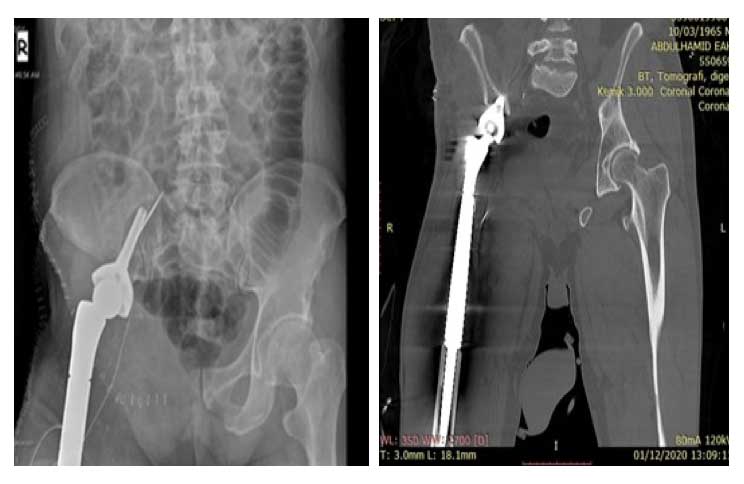

Ameliyat Öncesi: Röntgende sağ kalçaya çimentolu total kalça protezi ve asetabuluma titanyum plak uygulanımı ve asetabulum mediald tümör nüksü görülmekte.

Ameliyat Sonrası: Röntgen ve tomografi kesitinde rezeksiyon sonrası uygulanan tümör protezi görülmekte.